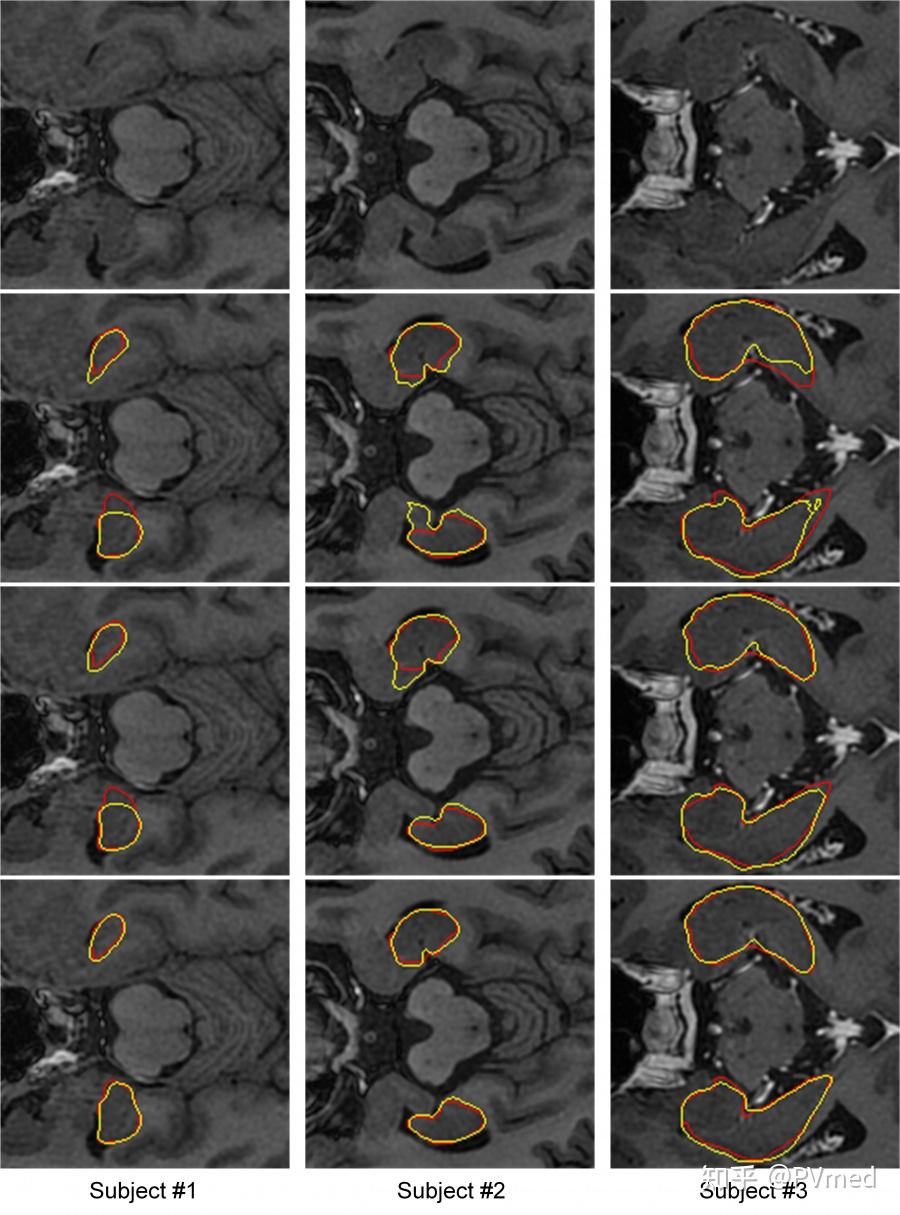

medical physics || 柏视医疗与山东省肿瘤医院海马体自动分割相关

图片尺寸900x1215